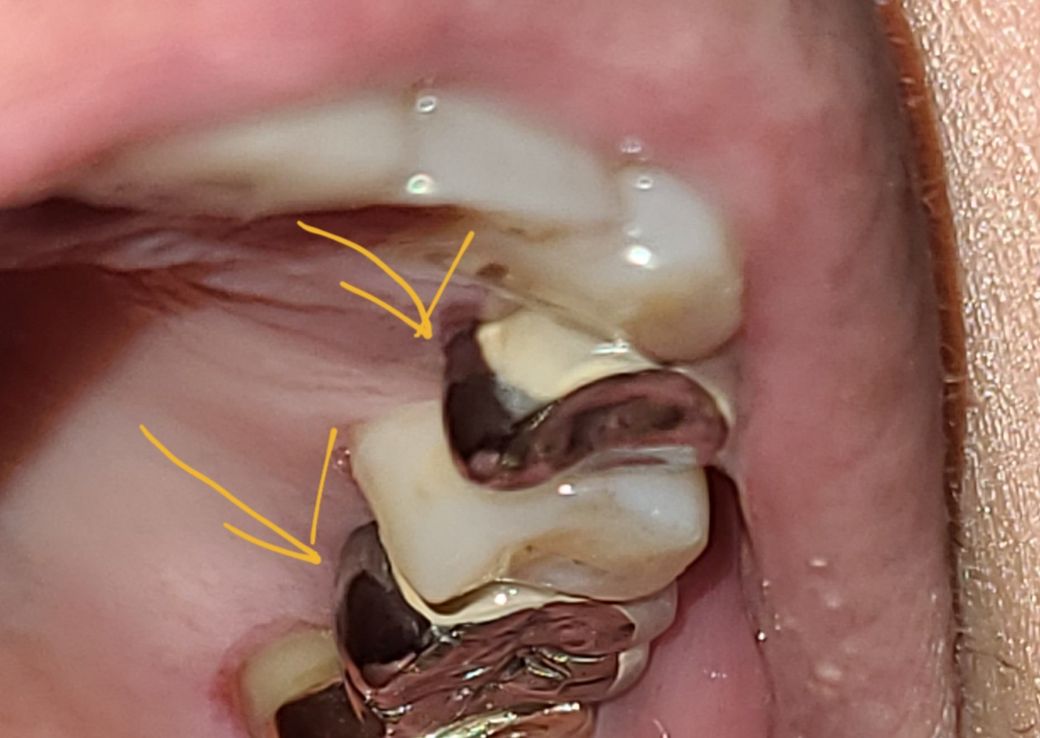

사진에 보시다시피 치아겉면만 도자기이고 저작면과 치아뒷쪽은 금속이 노출돼있는데요

pfm도 금속이잖아요 사진처럼 저렇게 금속노출이많은데 중금속 방출되나요?

PFM은 금속위에 도자기를 입힌 형태의 보철물입니다.

씹는 힘이 강하면 도자기가 깨질 가능성이 있으므로 씹는면과 보이지않는 입천장쪽은 금속으로만 제작하고 빰쪽만 도자기를 입힙니다.